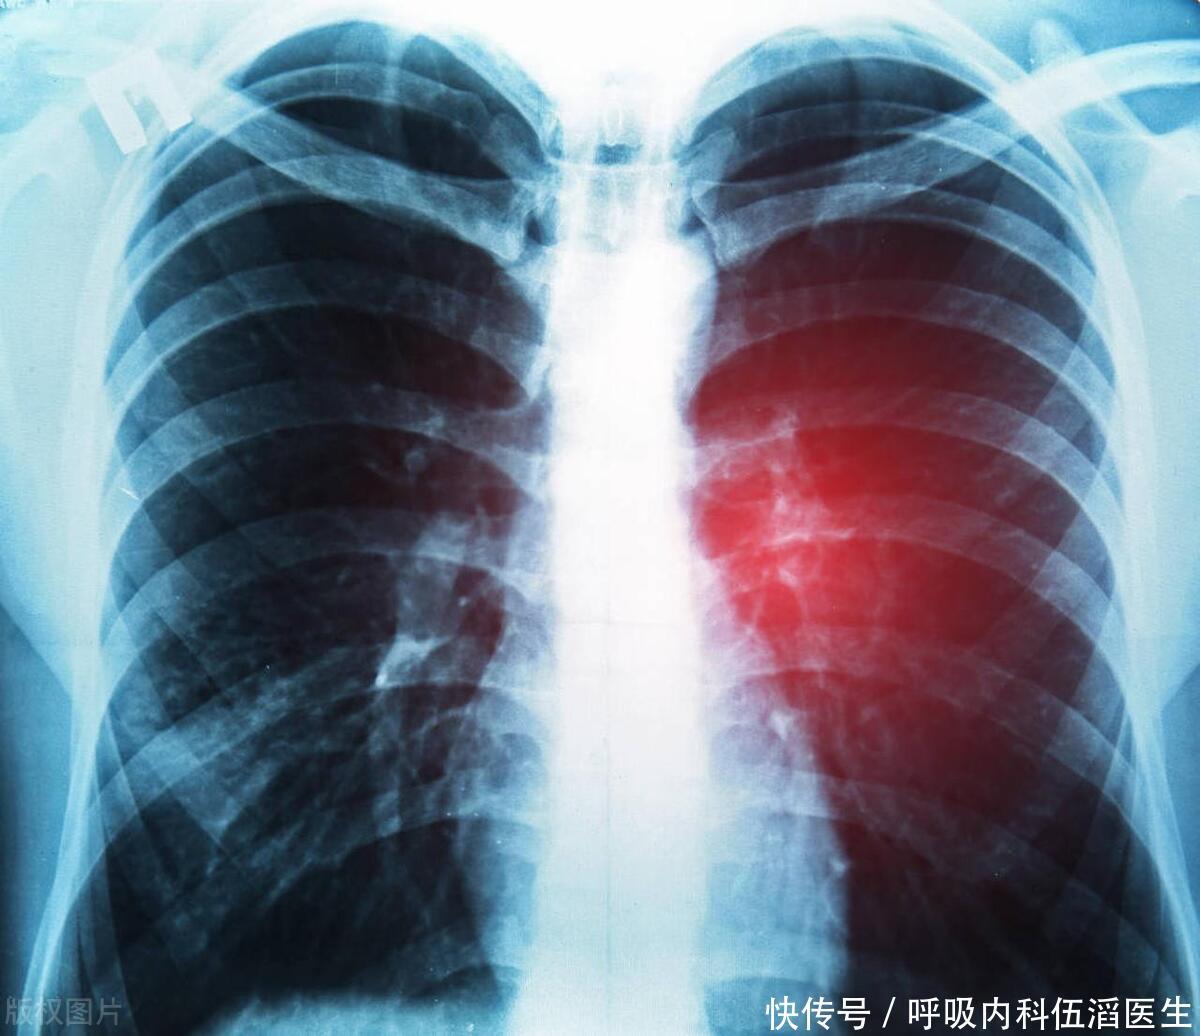

肺癌来临总是“不声不响”,提醒:身体有3个症状,胸部CT要早做

胸腔积液

声音嘶哑

肺结核